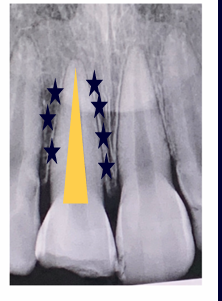

cervical root fracture

-outcome/treatment will depend on age of patient

-adult: don’t worry, can extract and implant

-child/adolescent: don’t want to extract- could compromise the alveolus; want to preserve the root, extract coronal segment, bury root under bone and use retention (essix retainer) for esthetics, when pt turns 18 could do implant then since the ridge will have been preserved